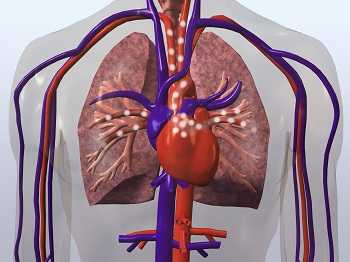

Cardiovascular diseases (CVD) are diseases that involve the heart or blood vessels. Among the many conditions that make up CVD are coronary heart disease, stroke (damage to the brain caused by a blood clot or intracerebral bleeding), and other diseases of the heart such as arrhythmia, cardiomyopathy, and heart valve problems. CVD is the leading cause of death in the United States 1.and worldwide 2. Health behaviors and factors that define cardiovascular health have been characterized 3. While it has been shown that more than half of those with CVD (53%) are less than 60 years old, and circulatory diseases are a leading cause of death and permanent disability among workers 4, 5, much is unknown about how occupational risk factors contribute to CVD. NIOSH researchers are investigating a wide variety of occupational factors potentially related to CVD. Some of NIOSH’s current areas of study, which address a range of workers, risk factors, and challenging research questions, are highlighted in this Topic Page.